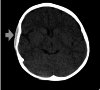

Sickle cell disease is an inherited disorder of haemoglobin formation, predominantly affecting individuals of African, Indian, or Mediterranean descent. Acute painful episodes frequently occur in these patients due to the blockage of small blood vessels by sickled cells, leading to tissue infarction. Two children of Nigerian descent, presented with severe headaches during a painful crisis episode with associated swelling on their scalps. CT imaging in both cases showed subgaleal haematoma which was managed conservatively in addition to managing the painful crisis with a good outcome. This report highlights the clinical presentation, diagnostic approach, and management of this uncommon complication of sickle cell anaemia.